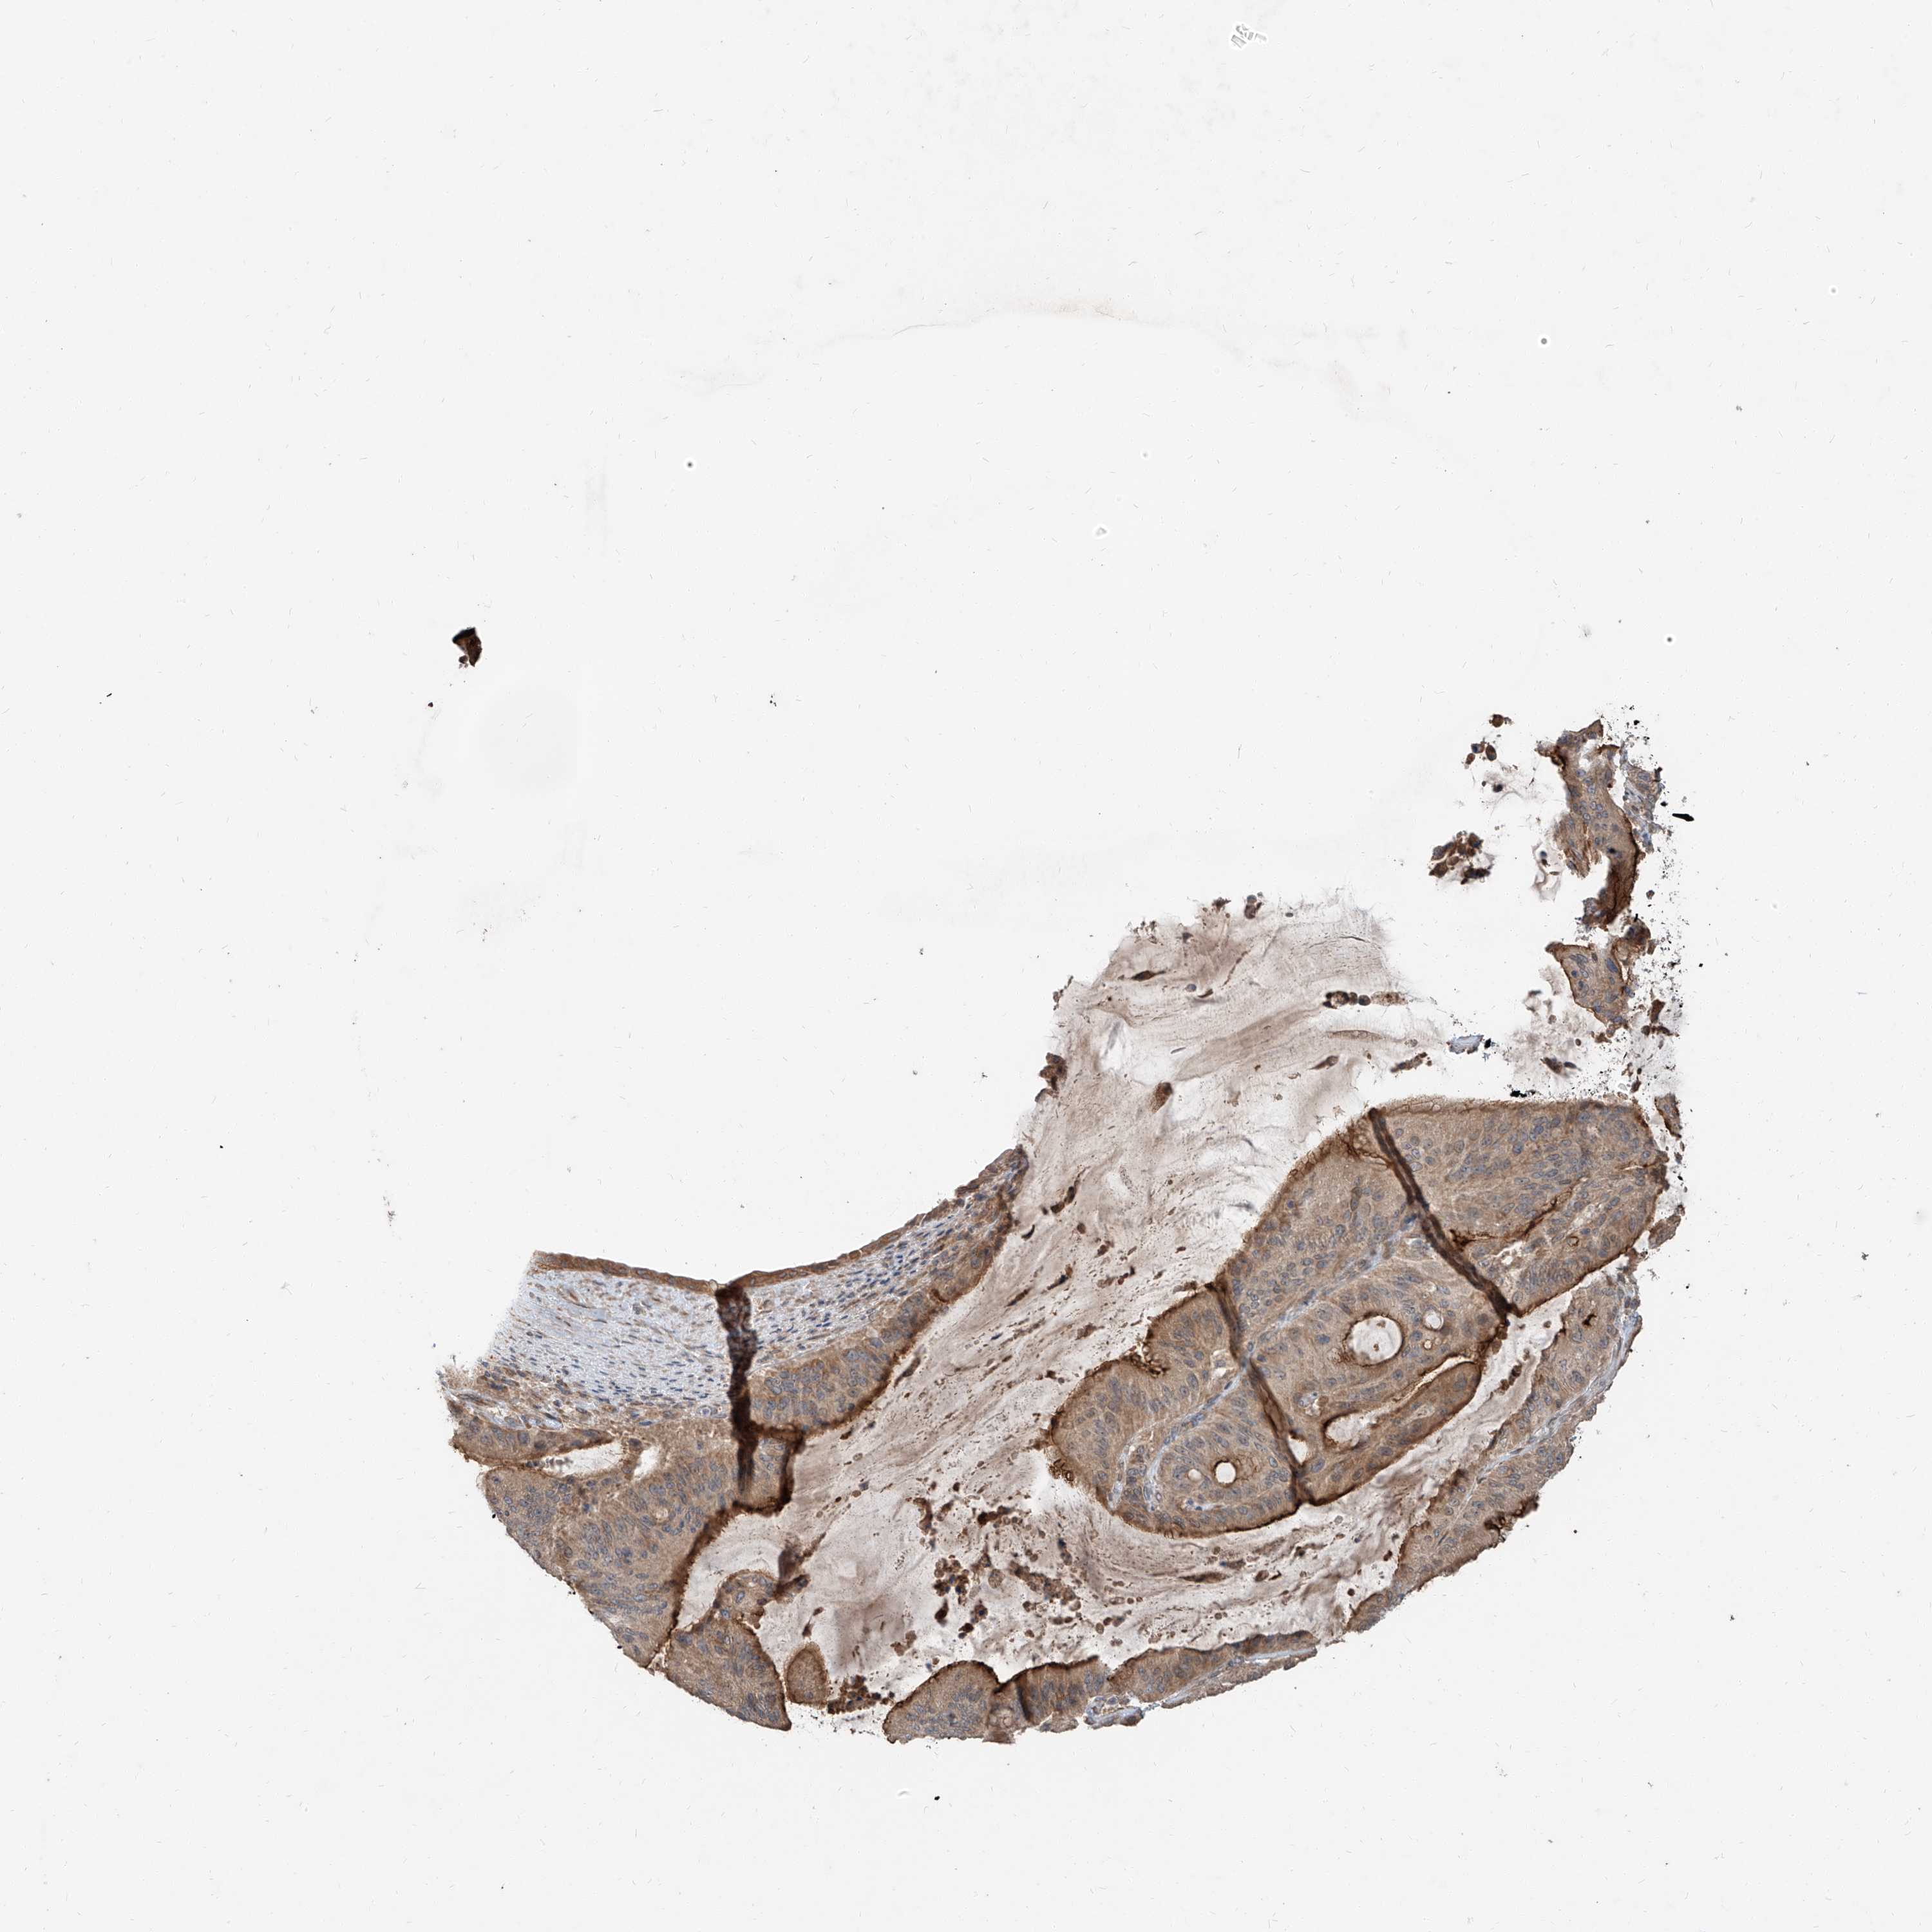

LIVER CANCER - Protein expressioni

A mouse-over function shows sample information and annotation data. Click on an image to view it in a full screen mode. Samples can be filtered based on level of antibody staining by selecting one or several of the following categories: high, medium, low and not detected. The assay and annotation is described here.

Note that samples used for immunohistochemistry by the Human Protein Atlas do not correspond to samples in the TCGA dataset.

Antibody stainingi

Antibody staining in the annotated cell types in the current human tissue is reported as not detected, low, medium, or high, based on conventional immunohistochemistry profiling in selected tissues. This score is based on the combination of the staining intensity and fraction of stained cells.

Each image is clickable and will lead to virtual microscopy that enables deeper exploration of all samples and also displays staining intensity scores, fraction scores and subcellular localization as well as patient and tissue information for each sample.

Antibody HPA030604

Staining

High

Medium

Low

Not detected

Intensity

Strong

Moderate

Weak

Negative

Quantity

>75%

75%-25%

<25%

None

Location

Nuclear

Cytoplasmic/membranous

Cytoplasmic/membranous,nuclear

Cholangiocarcinoma

Carcinoma, Hepatocellular, NOS